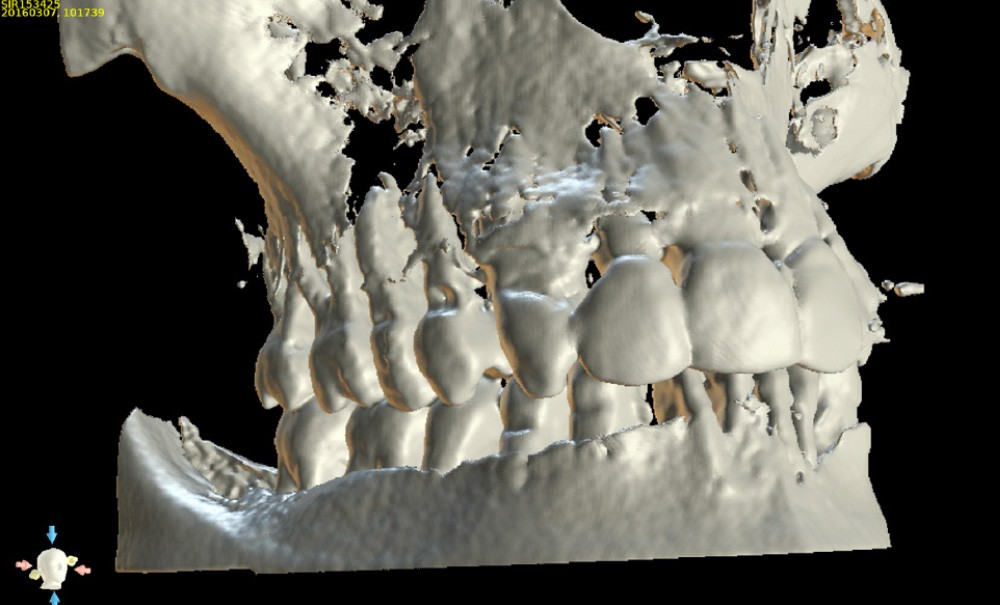

Le développement croissant des systèmes d’imagerie 3D à faisceau conique (CBCT : Cone Beam Computed Tomography), couplé à une démocratisation des logiciels de navigation et de planification implantaire, jusqu’à récemment onéreux, a permis une systématisation et une généralisation de leur utilisation à toutes les situations cliniques, rendant notre geste clinique plus prédictible.

Nous allons décrire, étape par étape, les différents temps cliniques permettant l’élaboration d’un guide chirurgical et la place de la CFAO de la planification à la réalisation du temps chirurgical au travers d’un cas clinique (fig. 1).